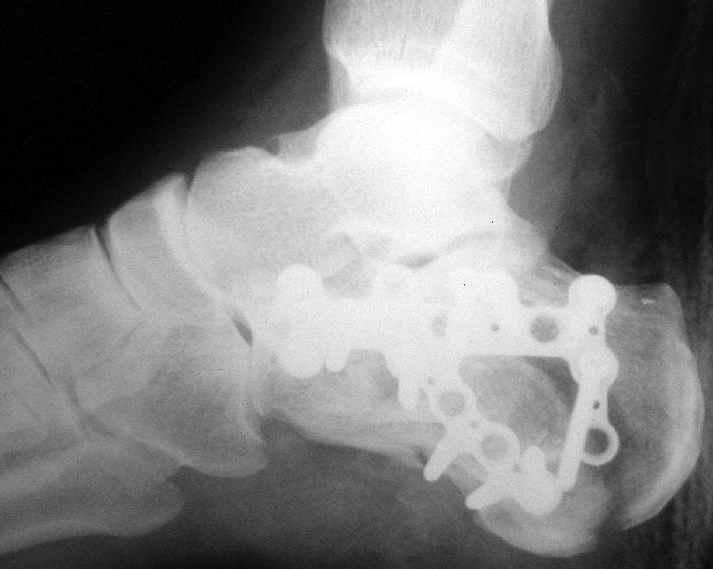

Окончательная фиксация спицами, пяточными пластинами (5) , в последнее время стали применять крючковидные пластины (ДЕОСТ) (6,6a).